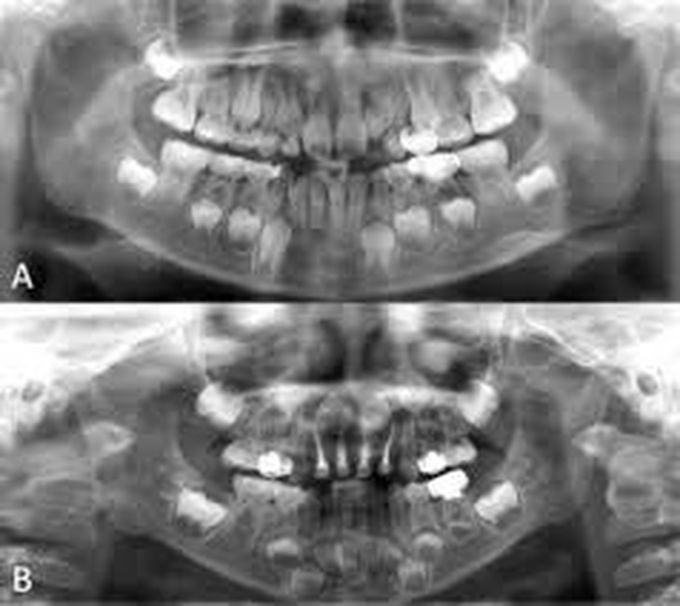

Hyperhypodontia

The simultaneous occurrence of hypodontia and supernumerary teeth in the same individual is termed as "concomitant hypohyperdontia" and it is an uncommon condition with the etiology still unknown.